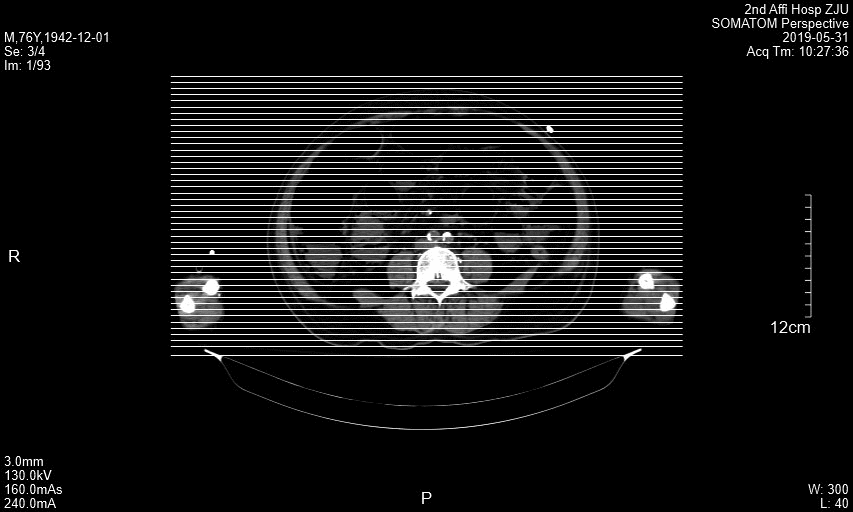

附图1 患者横断面CT图